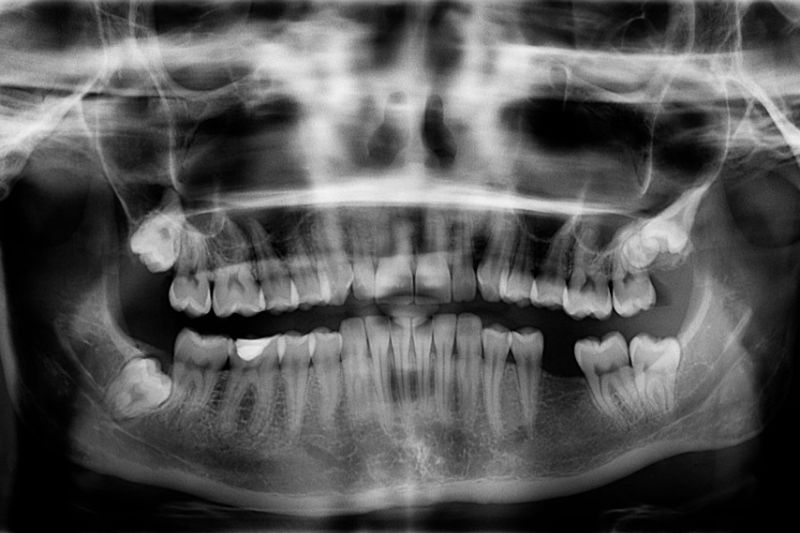

– Comprehensive oral examination

– Digital X-rays to assess tooth position